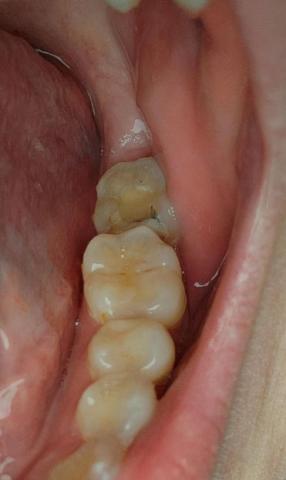

The image shows posterior molars/premolars with visible occlusal surface discoloration, dark pits, and irregular enamel texture. One tooth presents brown-black staining within fissures, strongly suggestive of active dental caries or recurrent decay under an old restoration.

Tooth-by-Tooth Visual Assessment

Tooth 1 (Most Posterior Visible)

Dark fissure staining

Loss of natural enamel translucency

Possible early cavitation

High plaque retention area

Tooth 2 (Middle Molar)

Yellow-brown occlusal discoloration

Surface wear and staining

Early enamel demineralization suspected

Tooth 3 (Anterior Premolar)

Mild staining

Enamel largely intact

Lower immediate risk

Clinical Diagnosis (Visual-Based)

Primary diagnosis: Occlusal dental caries

Secondary concern: Enamel demineralization

Risk of progression to dentin involvement

Possible microleakage if an old filling exists

Deep Examination Findings

Caries likely confined to enamel → early dentin stage

No visible fracture lines

No obvious abscess or gum swelling

Tongue-side moisture suggests normal salivary flow